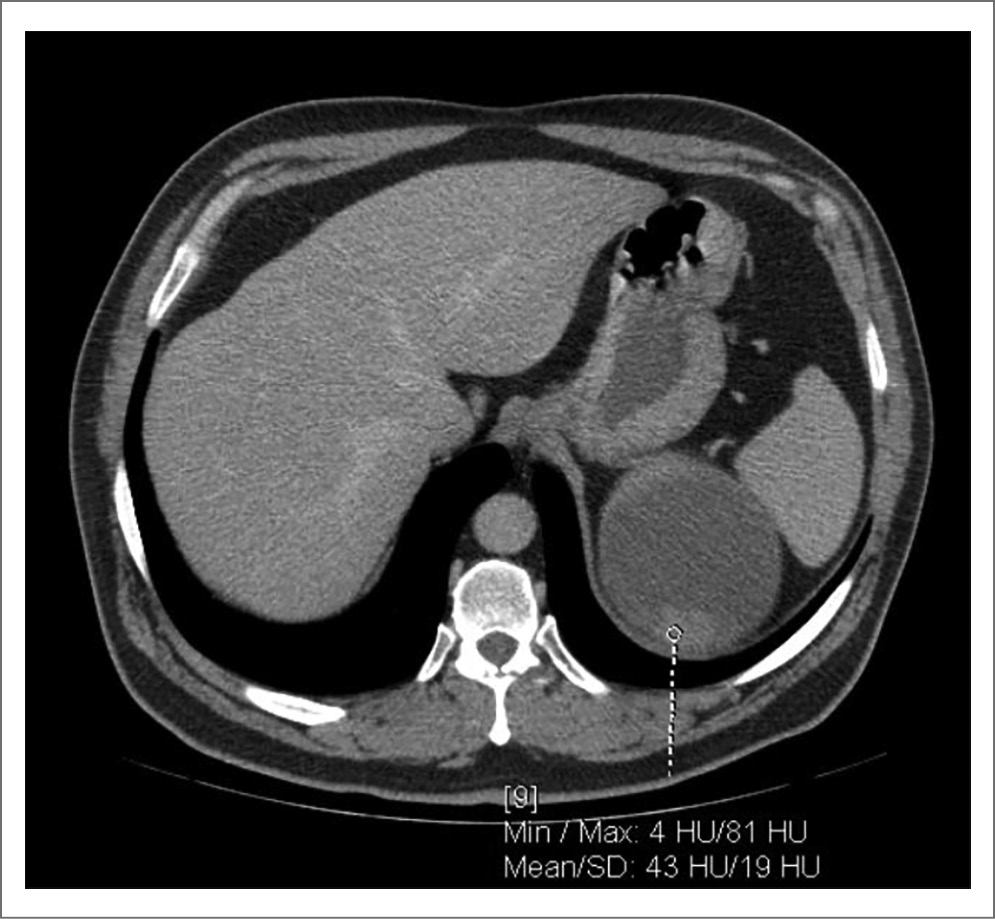

Стоит отметить клинический случай пациента из нашего исследования с кистой почки категории IIF диаметром до 131 мм в верхнем сегменте с тонкой капсулой и наличием пристеночного мягкотканного компонента, не накапливающего контраст. На рис. 1–4 представлены снимки мультиспиральной КТ пациента до операции с внутривенным контрастированием в различных срезах с демонстрационными измерениями. Выполнено оперативное вмешательство – лапароскопическое иссечение стенки кисты. В ходе операции после вскрытия стенки образования эвакуировано до 650 мл коричневой жидкости с желто-коричневыми хлопьями. При получении гистологического заключения верифицирован почечно-клеточный рак, проведена радикальная нефрэктомия в отсроченном порядке. Морфологическое исследование удаленной почки после повторного оперативного вмешательства подтвердило диагноз папиллярной карциномы, тип 2, G2 по Fuhrman. Т3N0M-R0.

Рис. 3. Киста левой почки. Плотность образования и накопление контрастного вещества в ангиофазу.